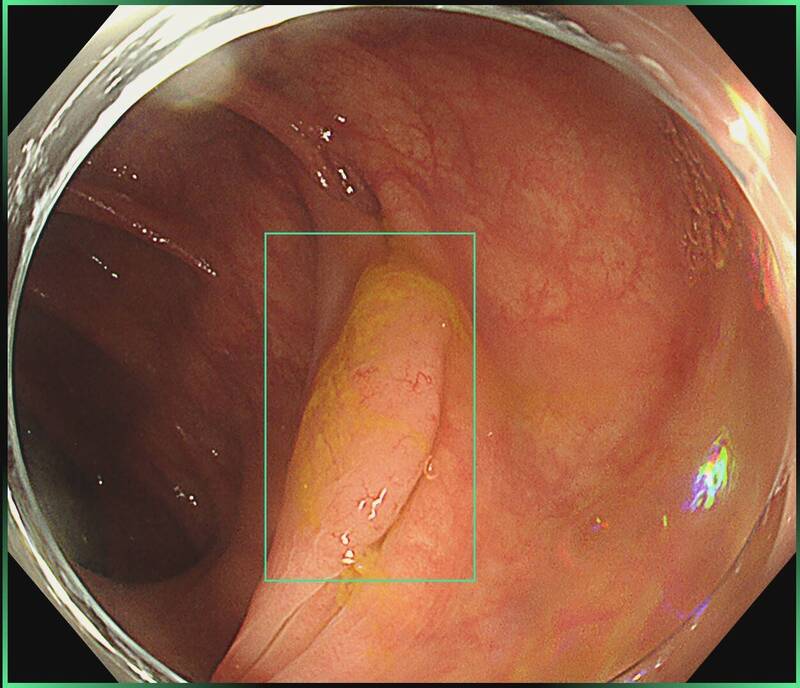

〔健康頻道/綜合報導〕若有大瘜肉,多數人會至醫院,但這類治療不能在診所嗎?禾馨民權內科診所腸胃科醫師葉秉威分享,有名40多歲女性,大腸內約有2.5至3公分的鋸齒狀瘜肉,就診時表示,希望在診所進行手術。經評估後,決定安排水下內視鏡黏膜切除術(UEMR)完整摘除瘜肉。在接受切除手術後,該名患者恢復良好,也沒併發症發生,病理也證實完整切除,免去病患的煩惱。

針對該名患者使用的水下內視鏡黏膜切除術優點,葉秉威在臉書專頁「胃腸專家 葉秉威醫師」發文說明,其不僅切除完整率、復發率較傳統內視鏡黏膜切除術高,併發症風險也與傳統方式相當。

對於大瘜肉的定義,葉秉威解釋,一般超過1公分大腸瘜肉,就叫做進階型瘜肉,也是認知中較大的瘜肉,因為這類瘜肉多帶著較高癌變風險,也較容易切不乾淨,或容易復發,因此需要醫師特別留意、小心切除。